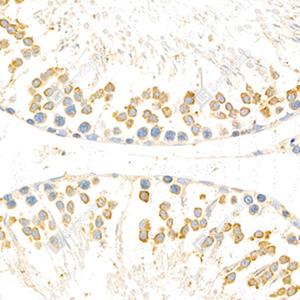

IHC检测Torsin A/DYT1蛋白(货号 GB111294). 样品: 大鼠睾丸, 4%多聚甲醛 (货号G1101) 固定12-24小时. 抗原修复: 柠檬酸抗原修复液(干粉, pH 6.0) (G1201), 98℃, 20分钟. —抗: 1: 800稀释, 4℃ 孵育过夜. 二抗: HRP标记山羊抗兔IgG (H+L) (货号GB23303), 1: 200稀释, 室温孵育1小时. |